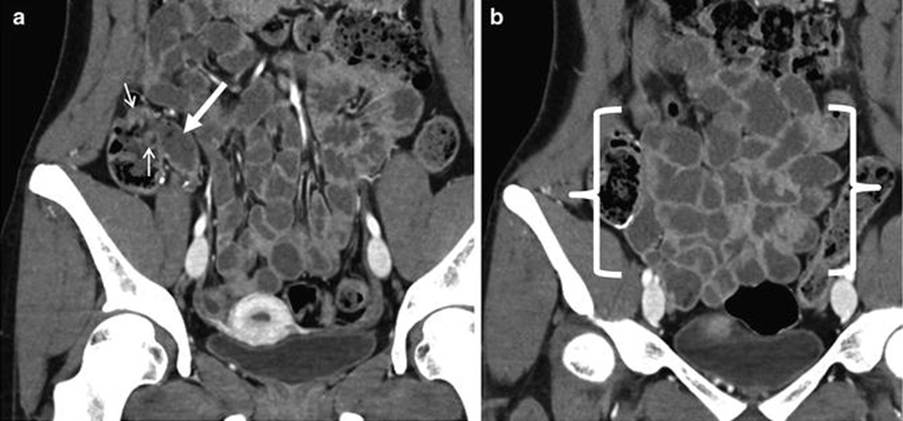

Coronal CT enterography images of the small bowel. The terminal ileum is presented at the white arrow. The small arrow indicates the ileocecal valve, which is the haustral fold of the caecum (first segment of the large intestine). The distal ileum is between the brackets. There are thin walls and decreased mural enhancement, which indicates inflammation or altered perfusion (Abdominal Key, 2017).